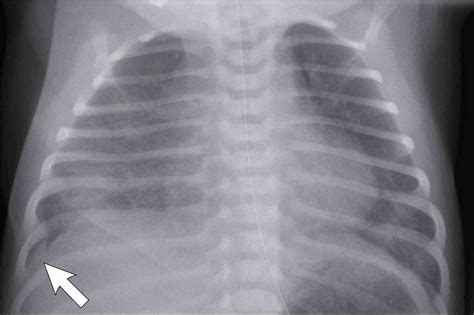

Infant X-ray imaging involves the use of low-dose radiation to produce images of the internal body structures. This technique is particularly useful for diagnosing conditions such as fractures, pneumonia, and congenital anomalies. The process is quick and relatively painless, making it suitable for infants who may be too young to cooperate with more complex diagnostic procedures.

• Diagnosis of Respiratory Conditions: Conditions like pneumonia can be detected through chest X-rays, allowing for timely intervention.

Pneumonia Chest X-rays can detect pneumonia, an infection of the lungs, by showing areas of inflammation or fluid buildup.